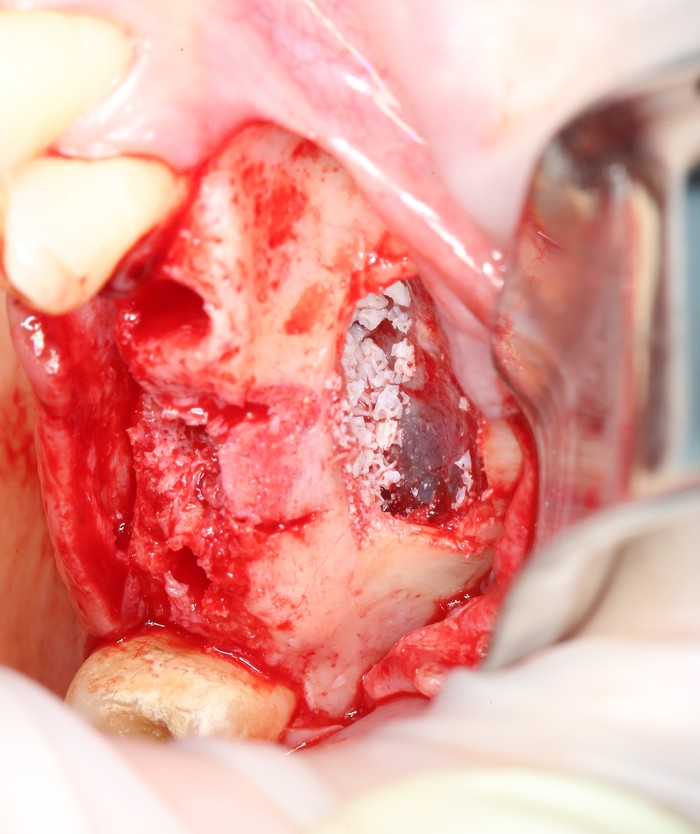

На верхней челюсти было дополнительно удалено два боковых резца с одномоментной установкой имплантатов, так же они были установлены в области четверок и шестых зубов. Дополнительно было проведено наращивание костной ткани - двусторонний синус - лифтинг. О том, что это такое, можно почитать ТУТ и ТУТ.